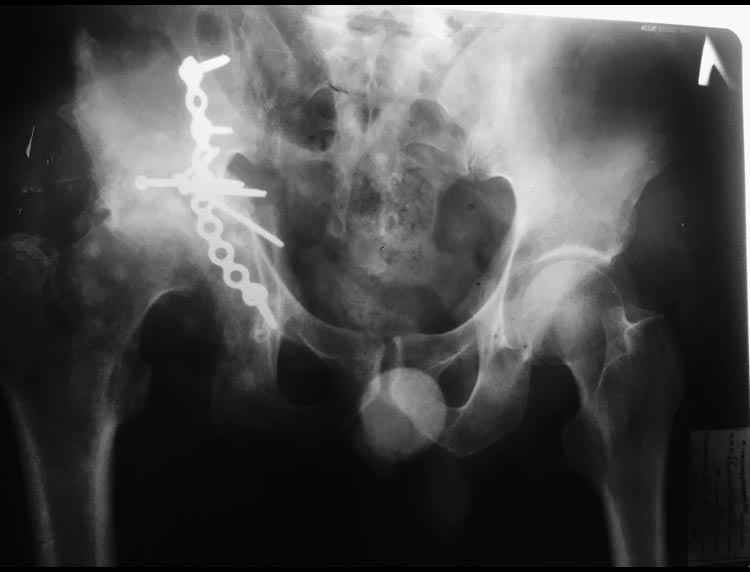

Перелом вертлужной впадины.

Через 4 месяца после травмы поступил в наше отделение. Пациенту выполнена операция : реконструкция вертлужной впадины с костной аутопластикой с гребня подвздошной кости ( дефект заднего края с полным лизисом костных отломков ). Фиксация пластиной Матта. На сегодняшний день ( через 7 месяцев после реконструкции впадины) отмечается лизис головки бедренной кости и укорочение абсолютной длины правой нижней конечности на 5 см. Есть сомнения на счёт сращения аутокости. Как быть в данной ситуации ? Спасибо

В настоящий момент головка бедра находится в положении задне-верхнего вывиха с дефектом

задней стенки и крыши. В настоящий лизиса головки нет? есть закономерный лизис задней стенки.

Головка цела ее очень хорошо использовать для пластики дефекта под укрепляющее кольцо ЭСИ

Головку лучше взяит вместе с шейкой - т.е. с кортикалом шейки - перевернуть ее кверху ногами, кортикал, фиксировать к надацетабулярной зоне, а головку опустить во впадину и расшарошить под кольцо.